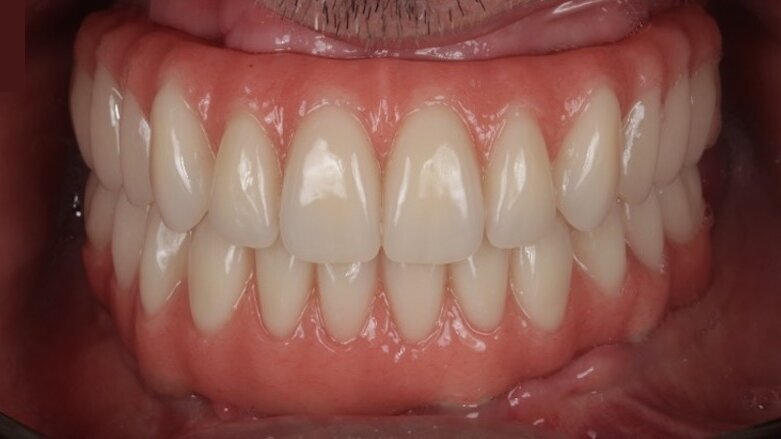

In a free webinar on Tuesday, 26 May, Dr Miguel Nobre will discuss the use of the high-performance polymer JUVORA PEEK as the ideal material for the prosthetic framework for implant restorations. (Image: Miguel Nobre)

There is increased interest in the long-term clinical outcomes and quality of life of patients treated with full-arch implant-supported dental prostheses with frameworks made of a high-performance PEEK polymer, rather than the traditionally used metals or ceramic materials. In a free webinar on Tuesday, 26 May, expert Dr Miguel Nobre will focus on the clinical outcomes for edentulous patients who have received full-arch implant-supported prostheses with JUVORA PEEK frameworks.

Dr Nobre, what makes the high-performance PEEK polymer you will be presenting in your webinar the ideal material for the prosthetic framework? We consider the high-performance JUVORA PEEK polymer to be the ideal prosthetic framework owing to the material’s light weight, resilience and shock-absorbing characteristics that, when applied to full-arch restorations, mimic the behaviour of natural teeth; as well as the capacity to produce such a framework through CAD/CAM.

Does the material also have its limitations? Yes, it has, just like all materials. The limitations include the colour of the material, but this can easily be overcome in full-arch restorations (as we use it as the framework) and together with other materials in veneers (ceramic, acrylic or composite).

What are the three main learning objectives for the viewers of your webinar? After the lecture, the viewers should be able to understand how to maintain excellence in the long term for the All-on-4 MALO CLINIC protocol for implant-supported rehabilitations, to identify the threats to the short-term and long-term success of All-on-4 rehabilitations and to recognise the potential impact of a PEEK framework on the successful outcome of All-on-4 rehabilitations.